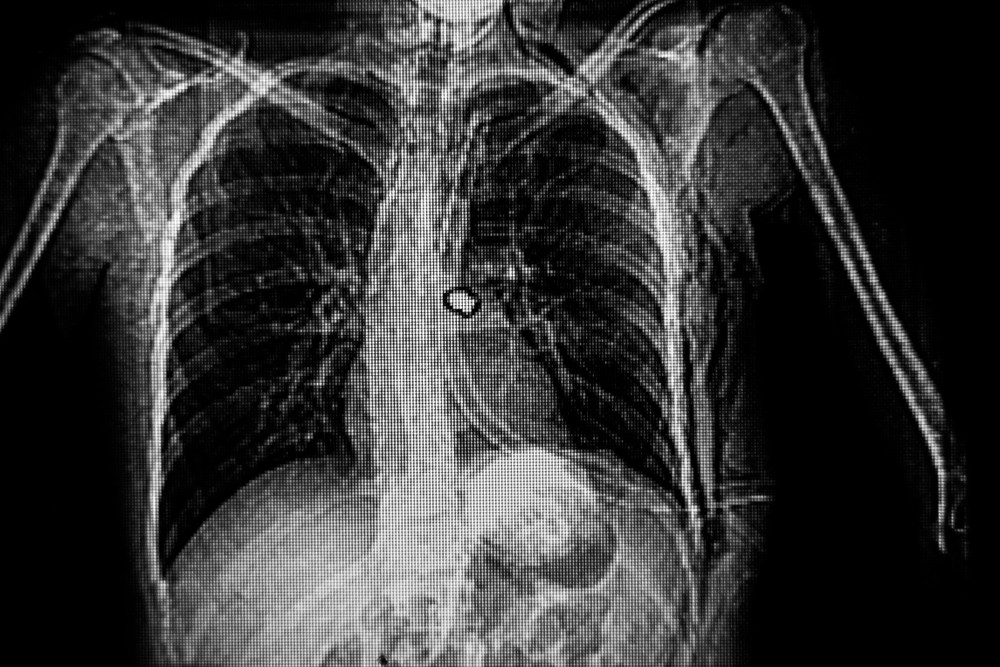

肺氣腫是一種慢性阻塞性肺病的病症之一,是由於空氣滯留在受損或彈性減弱的肺泡當中,使得肺部過度膨脹,充氣與肺容積增大,壓力不斷增加,甚至導致氣道壁破壞的病症,患者最終會因為肺衰竭、呼吸困難而死亡。